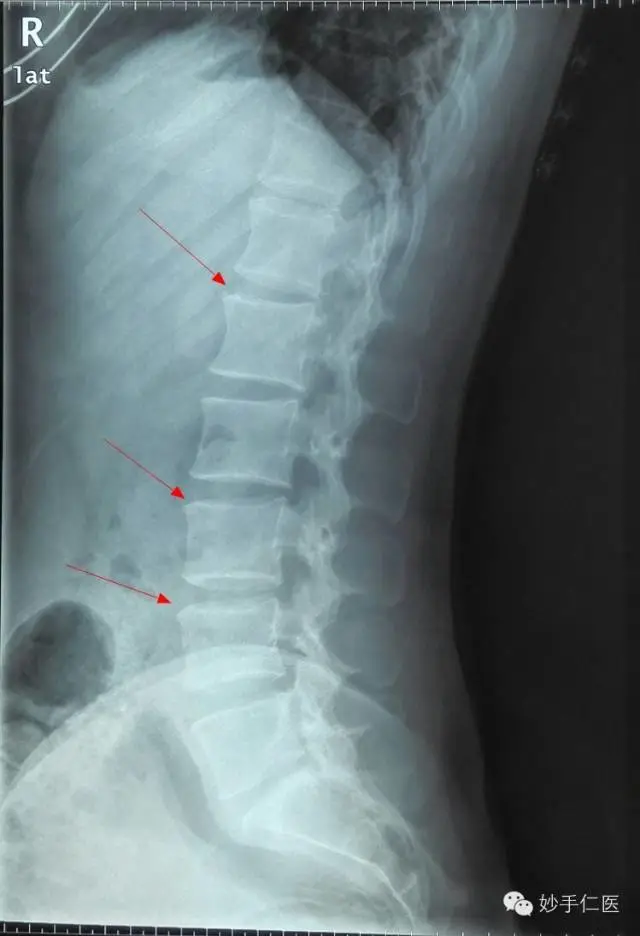

腰椎正位片子:腰椎存在脊柱侧弯,腰椎存在棘突旋转的状况,双侧髂骨高度不一致。腰椎和骨盆的片子,清晰的表明了人体力学结构的失稳,导致从腰部向上部分的力学状态破坏。通常来说,腰部问题和颈部问题都是存在联合出现的状况,毕竟,从根源来说,只是人体整体力学状态失稳的不同体现。